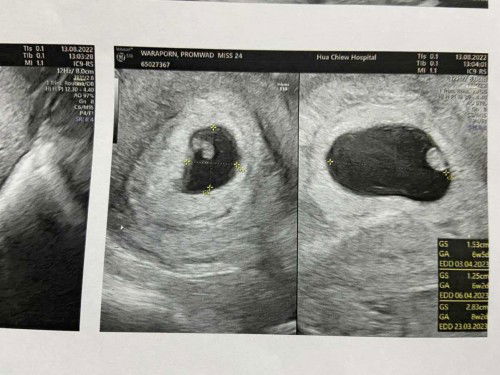

เจ็บท้องเหมือนปวดประจำเดือนมา 2-3วันแล้วค่ะ แต่ท้องไม่แข็งเลย วันนี้ไปหาหมอ....มีมูกเลือดตอนตรวจภายในแล้วค่ะ แต่ท้องไม่แข็งคุณหมอเลยให้กลับก่อน รพ.เชื้อเยอะ🥴😵💫 แม่ๆว่าน้องจะออกเมื่อไหร่คะ ระแวงมากเลย ไม่กล้านอน 🥹🥹🥹🤰🙏 ตอนนี้ 40+1ค่ะ ปล.จริงๆท้อง3 แต่ประสบการณ์2 ท้องแรกคือคลอดง่ายมาก ไม่เคยเจ็บแบบนี้เลย งงไปหมดแล้วค่ะ #ช่วยบอกกันหน่อยนะคะ #ท้องสาม #แม่ตั้งครรภ์